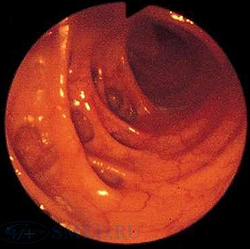

Колоноскопия является основным методом диагностики дивертикулита. Данное исследование позволяет провести дифференциальную диагностику заболевания с неспецифическим язвенным колитом, запорами, кишечной непроходимостью и опухолью толстого кишечника. Во время эндоскопии толстого кишечника при дивертикулите обнаруживаются поврежденные устья дивертикулов с воспалением слизистой оболочки вокруг них. Исследование дает возможность уточнить локализацию кровоточащих участков и оценить интенсивность кровотечения.

- Кишечная эндоскопия. Использование эндоскопических методов диагностики (колоноскопия, ректороманоскопия) показано только после купирования признаков воспаления. Колоноскопия является незаменимым методом поиска источника кровотечения, однако может способствовать появлению осложнений заболевания. Преимуществом эндоскопических методик является возможность проведения биопсии, морфологического исследования биоптатов.

Основным диагностическим методом выявления дивертикулов в толстом кишечнике является колоноскопия. Кроме того, при колоноскопии возможно выявить источник внутреннего кровотечения и исключить другие заболевания толстого кишечника. Ирригоскопия с контрастным веществом позволяет выявить выпячивания кишечной стенки.